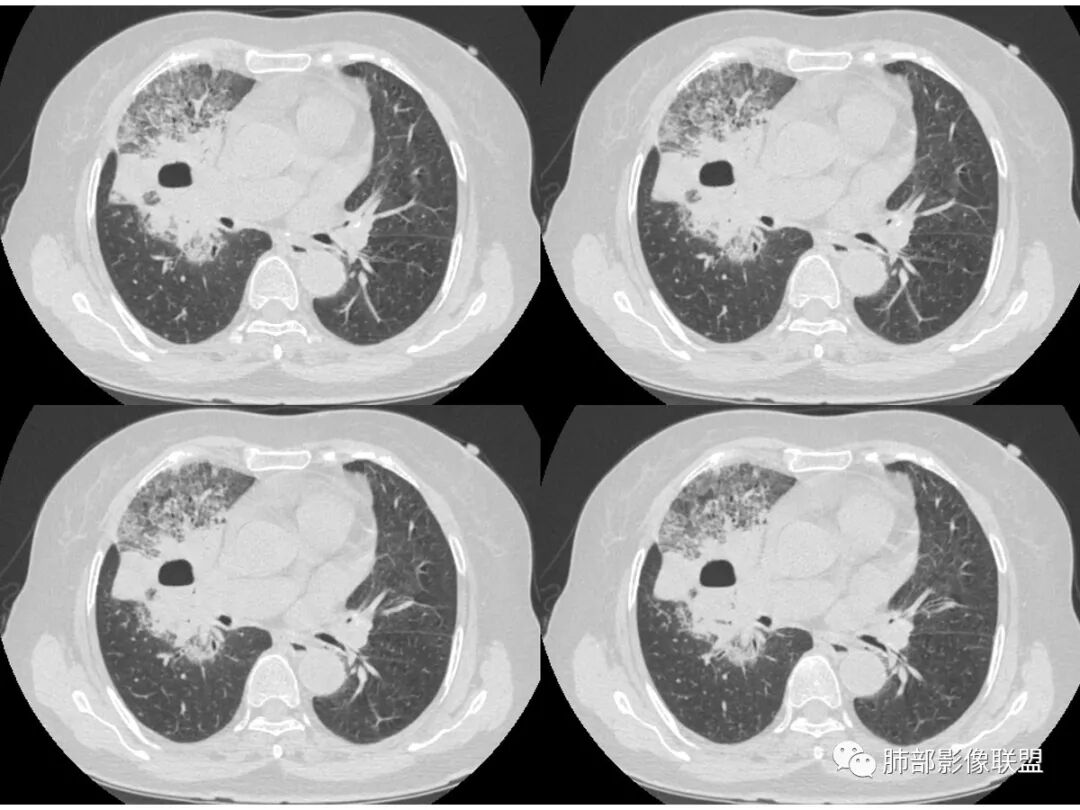

右肺上叶大片状阴影,内见僵硬的支气管,部分支气管轻度扩张,内见一空洞和液平,病灶边缘可见磨玻璃影,首先考虑恶性病变,粘液性腺癌伴感染可能。

老年女性,慢性病史,白色痰液,量多,病灶起于胸膜下,实性加磨玻璃,磨玻璃边缘偏轻,跨叶生长,病灶内可见枯树枝,考虑肺炎型肺癌。

老年女性,右肺上叶大片实变及磨玻璃密度影,磨玻璃边缘清晰,内可见小叶间隔增厚,内可见空洞,似可见分隔,叶间裂局部膨隆,纵膈窗,没有增强,枯树枝不明显,肺炎型肺癌可能,鉴别大叶性肺炎,结核?

胸CT:右肺上叶实变内可见支气管充气征,近端支气管狭窄,远端扩张,周围可见毛玻璃影,右肺中叶支气管闭塞,并可见气道壁钙化,右肺中叶体积缩小,实变内可见空洞,并可见气液平面,空洞周围可见毛玻璃样影,右肺下叶支气管开口狭窄,右肺门淋巴结肿大。纵隔窗可见病灶与壁层胸膜间隙增宽,考虑良性病变-----感染性病变------TB?

老年女性,无诱因咳嗽咳痰,白色粘液痰,抗炎治疗无好转,右肺多叶磨玻璃影,其内见枯树枝征,磨玻璃边界清,中间见实变影,且部分实变影内见空洞或局部支气管扩张,内壁光整,无纵隔淋巴结肿大,常规考虑粘液性腺癌,感染性病变待排,细菌性的排除,白细胞不高,不太支持,建议支气管镜检。

1.右上肺大片状影,周围有磨玻璃影,支气管截断征、枯枝征、远端支气管充气征,可见多个大小不等囊泡(支气管阻塞活瓣作用形成),病灶有少许收缩力感,叶间裂被稍牵拉内移;

病史老年女,白痰;影像实变,ggo多数边界清,病灶下缘部分不清,枯树枝,支气管近端阻塞、僵硬,病灶跨叶;病灶内空洞,有液平;间质增厚有结节感;肺炎型肺癌大于干酪性肺炎。

ggo边界清,远端支气管狭窄,常规考虑肺炎型肺癌;但这个空洞内壁光滑。

老年女性,咳白粘液痰;右肺上叶大片实变加GGO,局部膨隆也有收缩,见枯树枝征及坏死,考虑恶性~粘液腺癌,鉴别感染,血象不高。

老年女性,慢性病程,咳嗽伴白色粘液痰,无发热腹痛,糖尿病,白细胞及C反应蛋白不高,血沉快,铁蛋白高。胸部CT,右肺上叶大片状实变伴磨玻璃密度影,边界不清,边缘局部膨隆,叶裂弧形下坠,实变影宽基底与胸膜相贴;右肺下叶前基底段见类似病灶;右肺中叶不张并空洞形成,空洞内见气液平面;综合考虑右肺上叶及下叶肺炎型肺癌,右肺中叶结核。

白色粘液痰,枯树枝,支气管僵直,有空洞,磨玻璃,叶间裂膨隆、下坠,吴婧老师的肺炎型粘液性腺癌十大特点中占了好多条,所以考虑粘液腺癌,就差增强看看强化如何,血管如何了

老年女性,咳白色粘液痰,右肺跨叶大片高密度影,密度不均匀,其内见支气管枯树征,有空洞,边缘部分清楚,叶间裂有下坠膨隆感。考虑粘液腺癌,鉴别干酪性肺炎